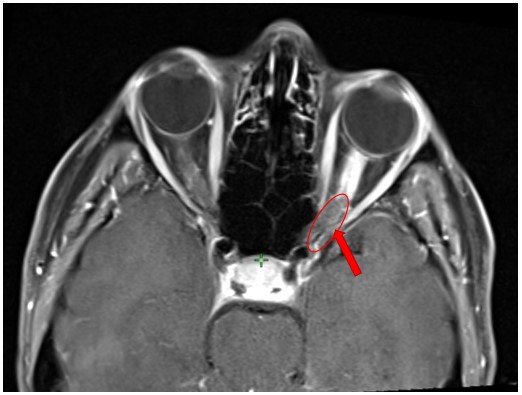

Mozak 22.12.2023. Bolesnica, rođena 1976. Meningeoma n. optici l. sin. fSRT (25 Gy/5x, 4/2021) Rezultat – 12 mjeseci nakon RK Kliničko poboljšanje vida ubrzo po provedenom zahvatu Smanjenje lezije uz dekompresiju živca